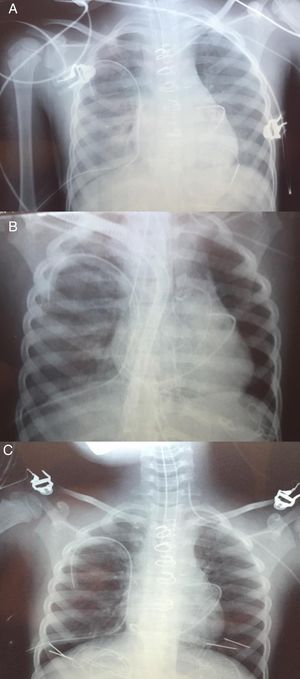

Cirugía. Con el diagnóstico de tetralogía de Fallot y ductus permeable se intervino realizándose cierre de ductus, cierre de CIV a través de AD, resección de zona hipertrófica de VD y parche transanular monocúspide del n.° 12 (Contegra®). El ecocardiograma intraoperatorio mostró ausencia de cortocircuitos residuales y un gradiente VD-pulmonar de 30mmHg. Tiempo de clampaje 88’, tiempo de CEC 170’. Se desconectó de circulación extracorpórea con ayuda de milrinona, dopamina y adrenalina 0,7, 5 y 0,2μg/kg/min, respectivamente. A la salida de quirófano la PA fue de 100/60mmHg, la FC de 160lpm, y la PVC de 14mmHg, lo que permitió ir descendiendo la dosis de adrenalina hasta 0,04μg/kg/min. El láctico a su llegada a UCIP fue de 2,8mmol/l. La radiografía de tórax inicial postoperatoria no mostró complicaciones. El primer día de postoperatorio se comportó hemodinámicamente algo inestable, por lo que no se progresó en el destete respiratorio, manteniendo una pO2 de alrededor de 80 con FiO2 de 0,4, PIP de 16 y PEEP de 10. A las 24h se decidió extubación, si bien en la placa de tórax se observaban cambios incipientes sugestivos de hiperaflujo pulmonar. Dos horas después de la extubación se produjo una desaturación súbita (86%) con hipoxemia (PaO256). Esta situación se mantuvo las siguientes 2h asociándose agitación, esputos hemoptoicos y fracaso de los intentos de ventilación no invasiva. Se procedió a reintubación urgente, observándose en la radiografía de tórax infiltrados intersticiales bilaterales, sin derrame pleural ni condensaciones (fig. 1A). El ecocardiograma no observó defectos residuales, estimándose una presión en VD por IT de 60mmHg (aproximadamente sistémica). Se conectó marcapasos transitorio por bloqueo AV completo de nueva aparición. Se observó una situación de oligoanuria y bajo gasto cardiaco que precisó el aumento de dosis de adrenalina hasta 0,4μg/kg/min, inicio de noradrenalina a 0,4μg/kg/min, así como comienzo de diálisis peritoneal. La situación respiratoria empeoró, produciéndose un aumento de las secreciones hemáticas por el tubo endotraqueal y dificultad para la oxigenación, con alta necesidad de FiO2.

Progresivamente la radiografía de tórax fue mejorando (fig. 1B), pudiéndose disminuir la asistencia el día +5 y ser retirada completamente el día +6, manteniéndose el esternón abierto y drogas vasoactivas (adrenalina 0,2, noradrenalina 0,8, dopamina 5, milrinona 0,7μg/kg/min) para mantener una PA 85/60 y una PaO2 de 78.